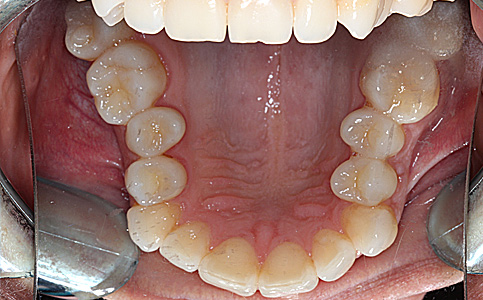

Przykład pełnej rehabilitacji protetycznej obejmujący leczenie biologiczne, uzupełnienie braków zębowych implantami oraz korony pełnoceramiczne w łuku górnym i dolnym. Spektakularna metamorfoza uśmiechu wykonana przez zespół Centrum Stomatologii i Ortodoncji FRESHmed odmieniła życie Pacjenta dodała pewności siebie i sprawiła, że z chęcią się uśmiecha.